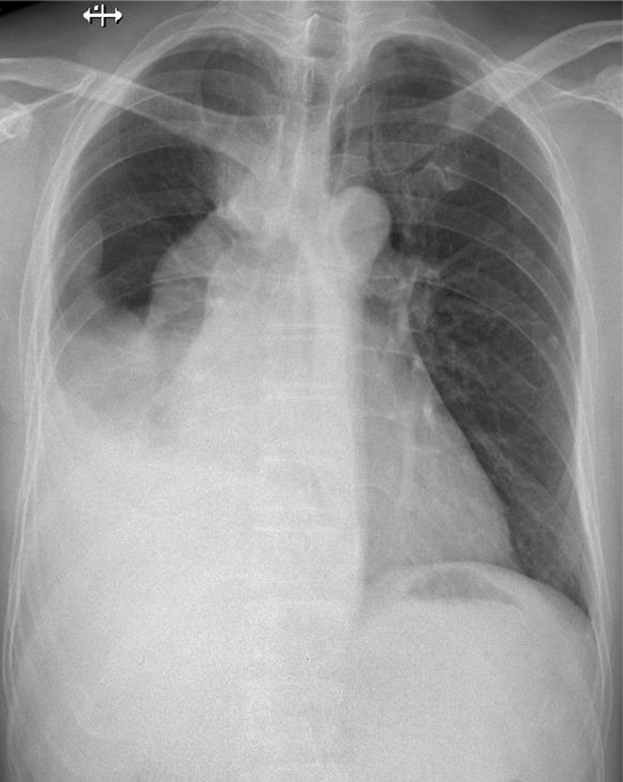

Hãy phân tích tình huống NAM 47 tuổi -CĐ:Tràn dịch màng phổi (P) nghi do lao

1-Tràn dịch màng phổi (P) lượng trung bình